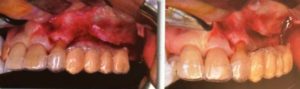

CADCAM チタンメッシュ

従来は高度の骨欠損部位に最終的に造りたい形をイメージして、チェアサイドでチタンメンブレンを曲げて適合させていた。しっかりと適合させるための賦形やそれにかかる時間が難点だった。

現在はCAD上で術前にチタンメンブレンの理想的な形態を設計し、CAMでチタンメンブレンを作成している。この方法により術中は適合を確認し、骨補填材料を詰めてスクリューで留めるというシンプルな術式になっている。